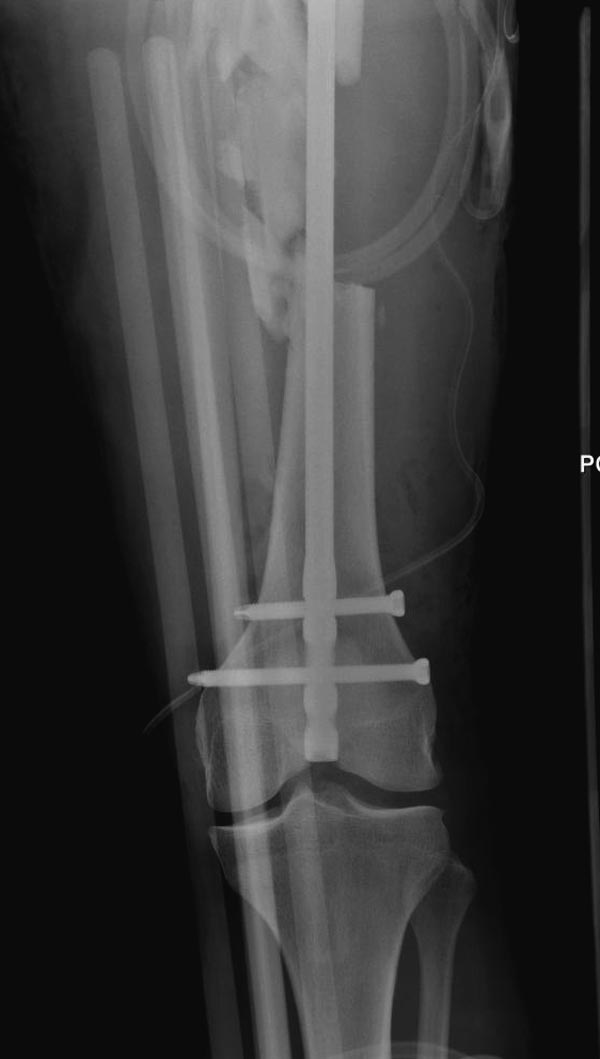

Здесь выставлен ренгенограммы больного, ему 21, травму получил в результате высокоскоростной погони на украденной машине, которая закончилась смертью трех остальных “боевых комрадов”. Начатую коллегой открытую операцию на шейке пришлось закончить мне, установкой винтов и ретроградной фиксацией бедра. Выписка в обычное сроки и наблюдался амбулаторно. Каждый раз напоминали о возможности осложнений ввиде несращения! По истечению 4 месяцев появились признаки варусной деформации. На СТ срезах несращение шейки и бедра. Риминг, замена на более толстый гвоздь и вальгусная остеотомия.

Сразу скажу, что пациент вчера (8.04) прооперирован - артротомия, остеосинтез мыщелков большеберцовой кости канюлированными винтами, открытая репозиция отломков бедренной кости, ретроградный БИОС, остеосинтез надколенника (центральных его отломков) спицами с проволочной петлей. Двухкратная попытка закрытой репозиции шейки на операционном столе после синтеза бедра - абсолютно неэффективна. Учитывая продолжительность и травматичность операции, шейка отложена на 2-й этап. Плечо наверное на 3-й (если вообще делать). Снимки постараюсь предоставить, но чуть позже.